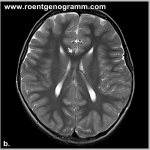

Чтобы подтвердить диагноз, определить причину болезни и определить состояние тканей, он направляет пациента на диагностику:

• рентгенографию;

• ультразвуковое исследование;

• денситометрию;

• компьютерную или магнитно-резонансную томографию;

• анализ крови на инфекции и аутоиммунные заболевания;

• анализ на онкомаркеры (при подозрении на наличие опухоли).